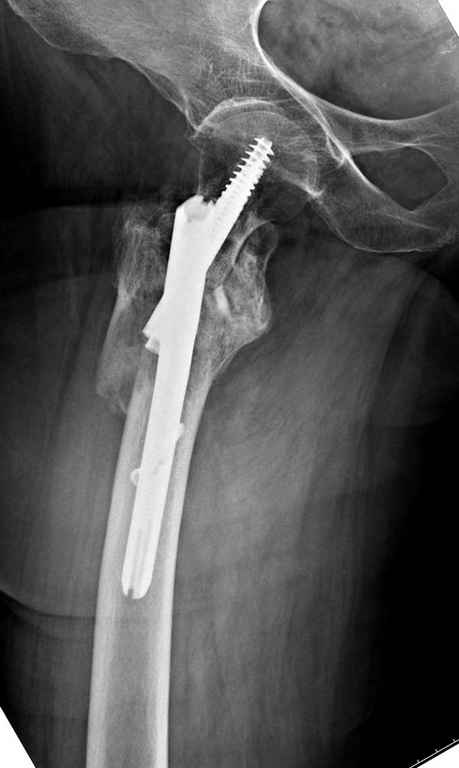

А что тут заставляет сомневаться? Здесь настолько очевидно предпочтителен закрытый интрамедуллярный остеосинтез реконструкционным стержнем (проксимальные гвозди толстоваты для такого молодого возраста), что закрадывается мысь о каком-то подвохе.

Не солидно экономить на пленке, это не делает чести презентации. Такие ограниченные нестандартные снимки приводят к тактическим ошибкам.

Предугадать распространение линий перелома при чрезвертельных и оскольчатых переломах трудно, поэтому для принятия правильного решения рекомендуется Компьютерно Томографические исследование.

При отсутствии КТ, снимок на вытяжении поможет увидеть общую картину расположения отломков, особенно потенциальные места введения импланта. Риск раскола в этом случае огромный, поэтому больной должен быть дообследован.

А так для лечения оскольчатых переломов подходят все методы, включая интра- и экстрамедуллярные в зависимости от опыта и наличия импланта.

Здесь пара похожих случаев.

Увожаемый коллега,мое мнение:фиксация и\медул.блок. стержнем Gamma-long "STRYKER". Вероятно, закрыто сделать полностью может не получится. Откроетесь на 6-8 см. для репозиции промежуточного фрагмента, но только после установки стержня. Удачи!!!